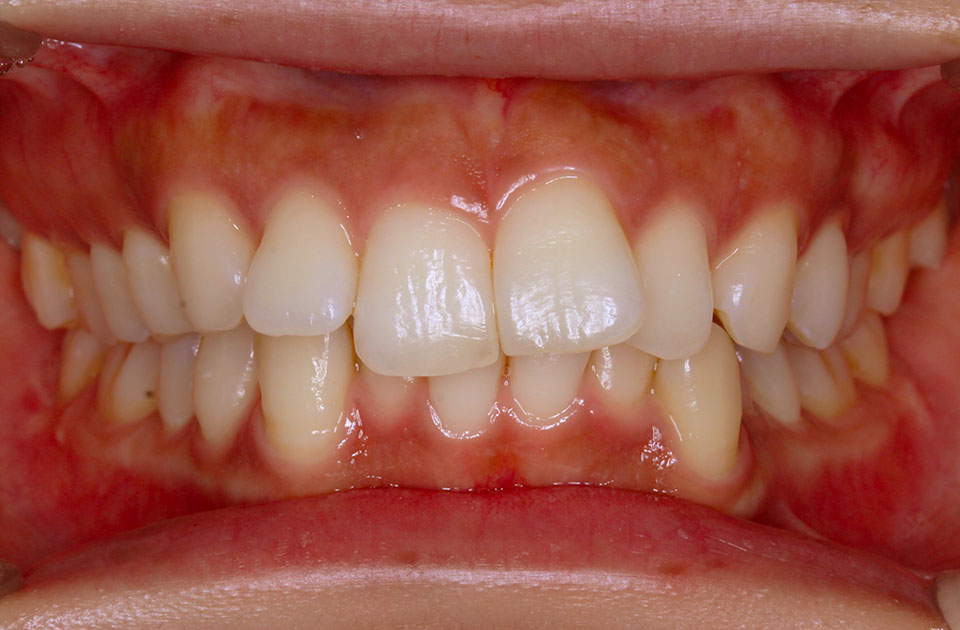

矯正前 正面

矯正後 正面

主訴 口元の突出感を治したい。ガミースマイルを治したい。

年齢 20代

治療法 上下顎マルチブラケット装置

抜歯の有無 上顎左右側第一小臼歯、下顎左右側第一小臼歯

治療期間 1年10ヶ月